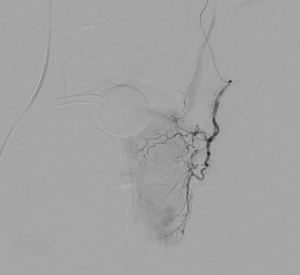

Overall, the procedure involves shrinking the prostate by treating its blood vessels. An interventional radiologist gains access through a small incision in the upper thigh or the wrist. From there, small particles are injected into the prostate to slow the blood flow to the gland, causing the prostate to shrink. Relief from BPH symptoms occurs in the following weeks and months. It is a relatively painless procedure using conscious sedation. After the procedure, UCSF Radiology follows up with patients at one, six and 12 months.